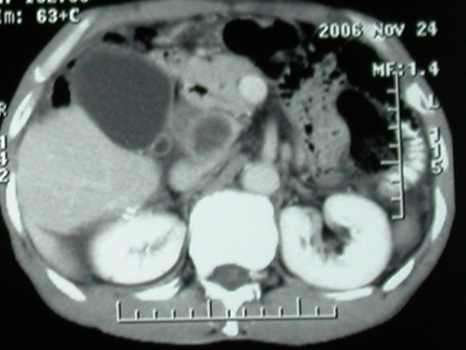

ct表现:1,胰腺钩突后方肿块,不均强化,中心密度低,钩突及门静脉前移。2:肝右后叶不均强化灶,突出肝表面,3:胆囊明显增大,肝内胆管及肝总管内积气。4:腹腔内少量积液。

补充一点重要资料:今日查afp大于正常值10倍以上。因此,本病例最大可能应该是肝癌。

手术结果:

肝脏尾状叶肝癌(沿肝十二指肠韧带向下韧带内生长,门腔间隙外压增大),大结节性肝硬化,胆囊积脓,胆道感染。术中见肝外胆道2cm直径,肿瘤向前压迫胆管至扁平状态。